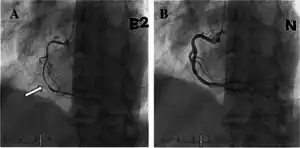

| a) Occlusion of mid portion of right coronary artery b) after injection of intracoronary nitrate shows resolution | |